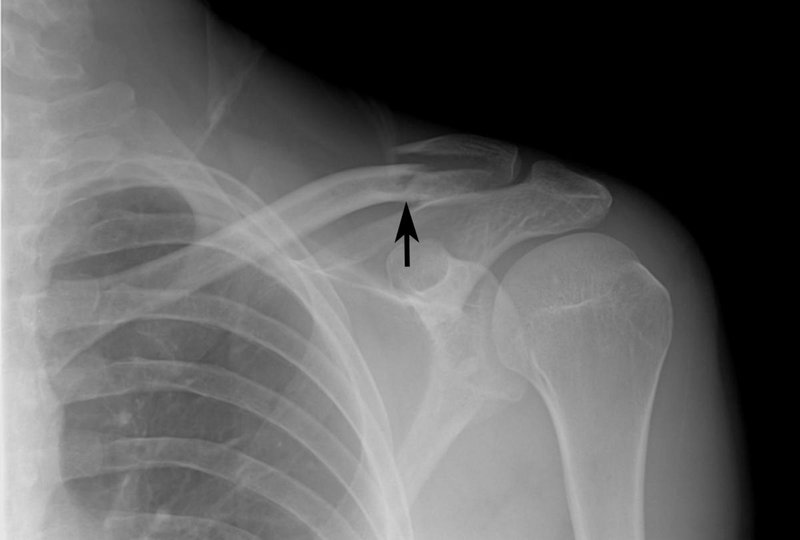

4/ Gãy xương

- Nếu bạn bị gãy xương vai do chấn thương nhẹ, điều này có thể liên quan đến một khối u ở vai có thể biến thành ung thư. Ung thư xương vai có thể làm suy yếu phần xương ở khu vực này gây nên tình trạng dễ gãy xương, đi kèm với đó là những cơn đau nhức đột ngột và dữ dội. Vết gãy có thể xảy ra ở vùng xương trước đó đã bị đau hoặc nhức trong một khoảng thời gian.